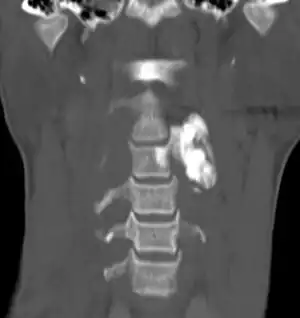

Osteogenic tumors, also known as bone forming tumors, are a type of bone tumor that can be non-cancerous (osteoma and osteoid osteoma), intermediate or locally aggressive (osteoblastoma), or cancerous (osteosarcoma).[1][2] There are ten subtypes and they are easier to distinguish than chondrogenic tumors.[1][2]

| Locally aggressive | Osteoblastoma NOS |